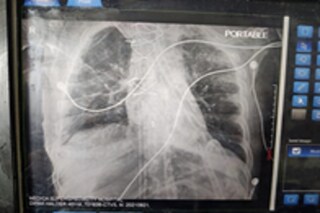

দীপক হালদারের করোনার চিকিৎসা চলছিল এবং তিনি ইসিএমও (ECMO) সাপোর্টে ছিলেন। সফলভাবে তাঁর দু'টি ফুসফুস প্রতিস্থাপন করে কলকাতার এই সুপারস্পেশ্যালিটি হাসপাতাল এক অন্যন্য নজির সৃষ্টি করেছে। পূর্ব ভারতের মধ্যে কলকাতাতেই প্রথম সফলভাবে, এমন ফুসফুসের প্রতিস্থাপন করা সম্ভব হল। এই অপারেশনের জন্য বিখ্যাত কার্ডিয়াক সার্জারি স্পেশালিস্ট ডাক্তারদের (Cardiac Surgery Doctor) নিয়ে গড়া হয়েছিল কার্ডিয়াক ক্রিটিকাল কেয়ার টিম (Cardiac Critical Care Team)।

দীপক হালদার তাঁর ফুসফুস প্রতিস্থাপনের জন্য ন্যাশনাল অরগ্যান অ্যান্ড টিস্যু ট্রান্সপ্লান্ট অর্গানাইজেশন (NOTTO) এবং রিজিওনাল অরগ্যান অ্যান্ড টিস্যু ট্রান্সপ্লান্ট অর্গানাইজেশনে (ROTTO) নিজের নাম রেজিস্টার (Register) করেছিলেন বলে জানা গিয়েছে। এর পর ন্যাশনাল অরগ্যান অ্যান্ড টিস্যু ট্রান্সপ্লান্ট অর্গানাইজেশনের মাধ্যমে গুজরাতের সুরাতের ইউনাইটেড গ্রিন হসপিটাল (United Green Hospital) থেকে ফুসফুস দু'টি সংগ্রহ করে কলকাতায় পাঠানো হয়। সুরাতের ৫২ বছরের মণীশ শাহ (Manish Shah) তাঁর এই অর্গ্যানগুলো দান করে গিয়েছিলেন। ২০ সেপ্টেম্বর তিনি ব্রেইন ডেথে (Brain Death) মারা যাওয়ার পর তাঁর ফুসফুস কলকাতায় এনে দীপক হালদারের শরীরে তা প্রতিস্থাপন করা হয়।